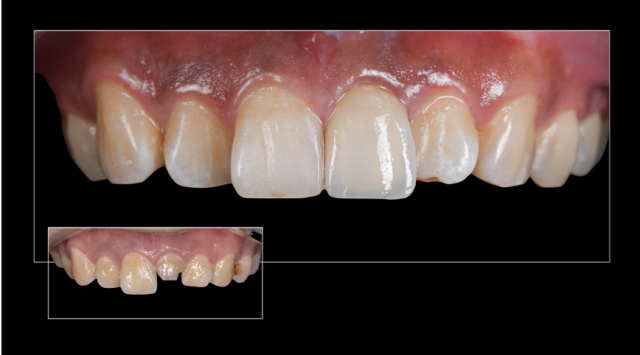

处理:口内试戴全瓷冠,检查就位情况、冠边缘密合无悬突、邻接关系紧密、外形及颜色患者满意、无咬合高点及咬合干扰,粘固修复体。

全冠边缘位置设计(龈上、齐龈、龈下):对于非美学区域,通常制备齐龈或龈上边缘,以减少预备过程中牙龈组织损伤,增加修复体的自洁性;而在美学区域,通常选择龈下边缘。本病例中因患者口腔卫生维护不是太理想,牙面由于菌斑生物膜的堆积导致牙龈炎,再者该患者属于低位笑线,结合患者实际情况,从远期效果考虑,与患者沟通,最终将该修复体边缘确定为齐龈边缘。